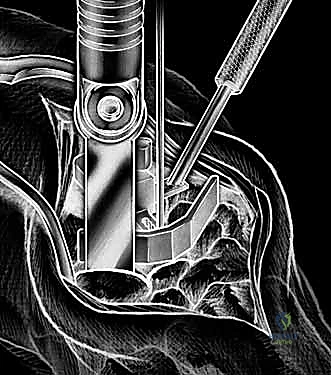

With the extensor tendons mobilized and safely retracted, a longitudinally based capsulotomy is performed. The capsule is reflected as radially and ulnarly based full-thickness flaps, exposing the distal radius and the entire carpus down to the base of the third metacarpal. Preparation of the distal radius involves scoring a reference line to ensure the DRUJ is preserved. The radial canal is sequentially broached to accept the modular radial stem. The modular radial stem component is designed to fill the distal radius canal to prevent loosening and provide rotational stability. While approved for implantation with bone cement (PMMA), most modern wrists are implanted with press-fit, cementless fixation to encourage osteointegration. Cement is generally reserved for cases of significantly compromised bone stock, severe osteopenia, or revision scenarios.

Carpal preparation requires exacting precision. Using the Maestro system as the archetype, the carpal resection guide is positioned to allow resection of 2 to 3 mm of the capitate head. It is provisionally held in position with two 0.062-inch Kirschner wires. The first wire is placed into the capitate neck and the second into the metaphysis of the third metacarpal, ensuring that the guide is perfectly parallel to the third metacarpal axis. With proper placement, the ulnar guide wing will lie close to the triquetrum–hamate articulation, and the radial wing will bisect the scaphoid at its distal third.

With the wrist held in neutral, the radius is scored through the cutting slot in the guide to provide a reference for the distal radial resection. The thumbscrew on the carpal resection guide is loosened to allow insertion of the radial resection guide boom. Following radial resection, the scaphoid, capitate head, hamate edge, and triquetrum are resected at a precise 90-degree angle to the axis of the forearm jig. The trial carpal plate is provisionally determined by the curvature and width of the remaining proximal carpal surface; it must lie flush with the hamate and proximal capitate surfaces. Unlike older designs, it is not always necessary to attempt fusion of the distal pole of the scaphoid to the surrounding carpus. The Maestro Wrist has a provision to replace the entire scaphoid using a carpal plate incorporating a modular radial augment, of which three separate sizes are available.

Following capitate reaming, the chosen carpal plate and stem are assembled and inserted into the capitate and seated onto the resected carpal surface. The carpal plate is anchored to the carpus with a radial screw that optimally does not penetrate the second metacarpal, and a second screw placed ulnarly into the hamate. This construct ensures stable distal fixation while avoiding the deleterious lever arm of a long metacarpal stem. Trial reductions are performed to assess stability, range of motion, and impingement. Once kinematics are confirmed, the definitive ultra-high-molecular-weight polyethylene (UHMWPE) body—which is direct compression molded onto a cobalt chrome alloy radial body—is impacted. The capsule and extensor retinaculum are meticulously repaired to prevent extensor tendon bowstringing and provide a robust soft tissue envelope over the implant.